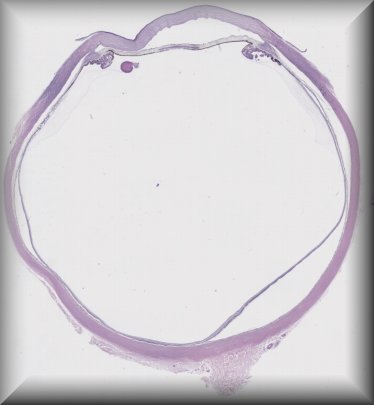

Caroline Thaung (London): Enucleation after breast cancer. |